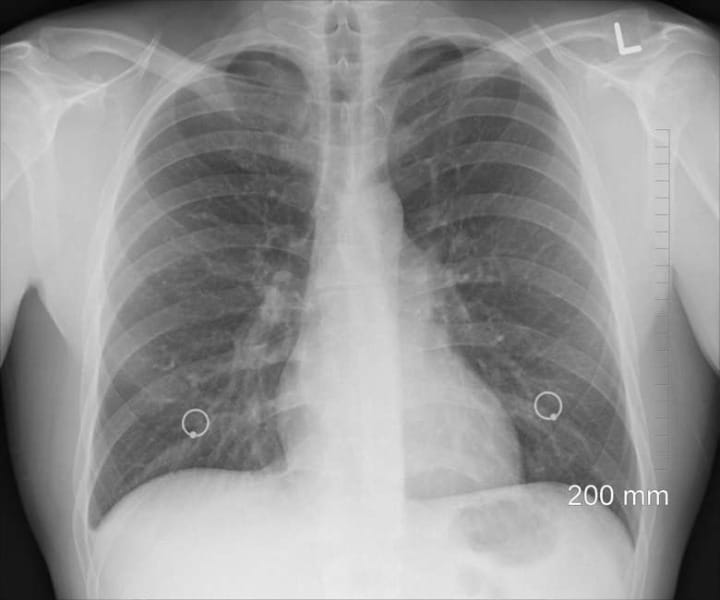

O tumor pulmonar é diagnosticado por exames de imagem, como raio-x e tomografia computadorizada do tórax e para sua identificação, é realizada a biopsia e um exame molecular, capaz de identificar o desenvolvimento da doença. Especialistas citam que a principal causa de câncer no pulmão é o tabagismo. Desta forma, a recomendação para evitar a doença é não fumar e manter distância de quem fuma. Quando o câncer é identificado precocemente, as chances de cura são maiores. O recomendado é que fumantes e ex-fumantes devem iniciar o rastreamento da doença a partir dos 50 anos.